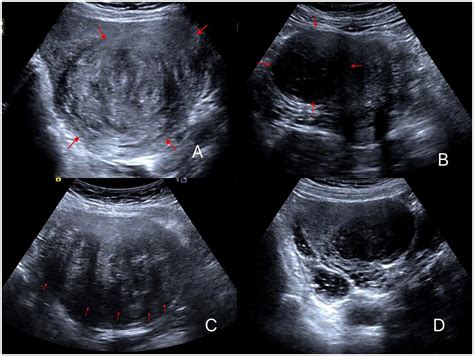

• Ultrasound: An ultrasound uses sound waves to create images of the uterus and can help identify the size and location of fibroids.